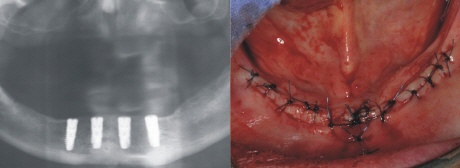

Planung der Implantatpositionen

In der Planungsphase wird entsprechen den Wünschen des Patienten die Anzahl und Position der Implantate festgelegt. Dazu muß eine sogenannte Übersichtsaufnahme des Kiefers gefertigt werden (Bild oben links). Zusammen mit der Begutachtung der Situation im Mund des Patienten (Bild oben rechts) können nun die Durchmesser und die Längen der Implantate geplant werden. Eine Analyse der Zuordnung des Oberkiefers zum Unterkiefers zeigt dem Behandler, wo die strategisch beste Position der Implantate im Hinblick auf die spätere Nutzung für die Prothese ist.